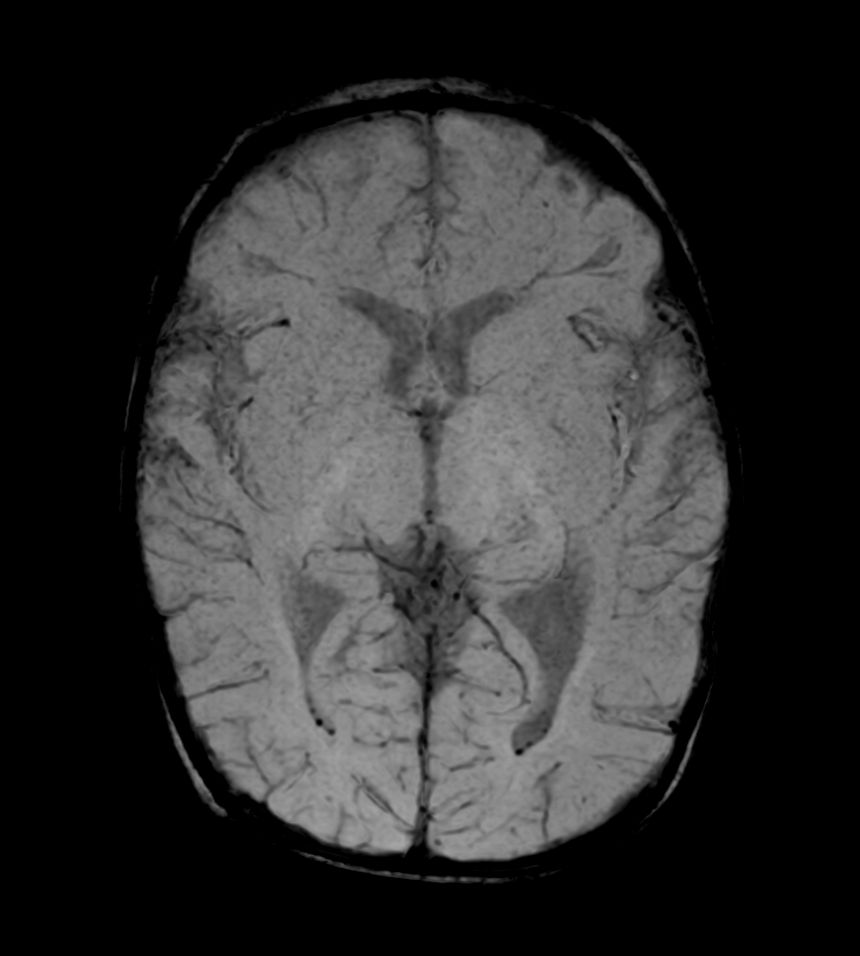

Axial SWIp